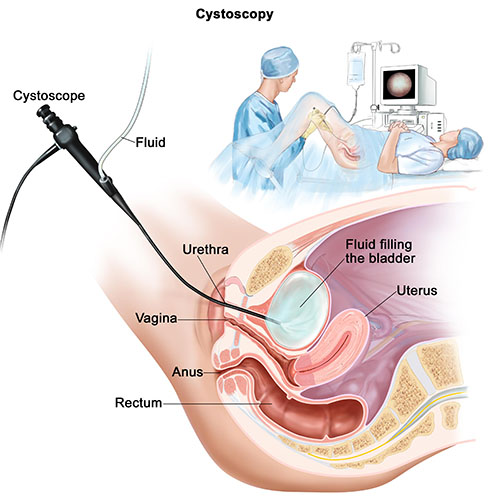

Transurethral Resection of Bladder Tumours (TURBT)

Transurethral resection of the bladder is a surgical procedure whereby the bladder tumours are removed from the bladder wall. This procedure allows our team of urologists to safely remove tumours or abnormalities as minimally invasively as possible, while preventing the cancerous tissue from spreading.

TURBT is one of the best treatment options for patients with bladder cancer. Unlike traditional operations that often involves the removal of the bladder through open surgery, and the placement of a stoma (a small spout-like hole in the abdomen) which can greatly affect the patient’s quality of life, TURBT allows patients to maintain their quality of life while overcoming a potentially harmful disease.

Transurethral resection of bladder tumours typically cause minor side effects that clear up within a few days. These side effects include:

- Burning sensation when urinating

- Mild discomfort

- Change in the force of urine stream

- Blood in the urine, causing red, dark burgundy, or brown colour